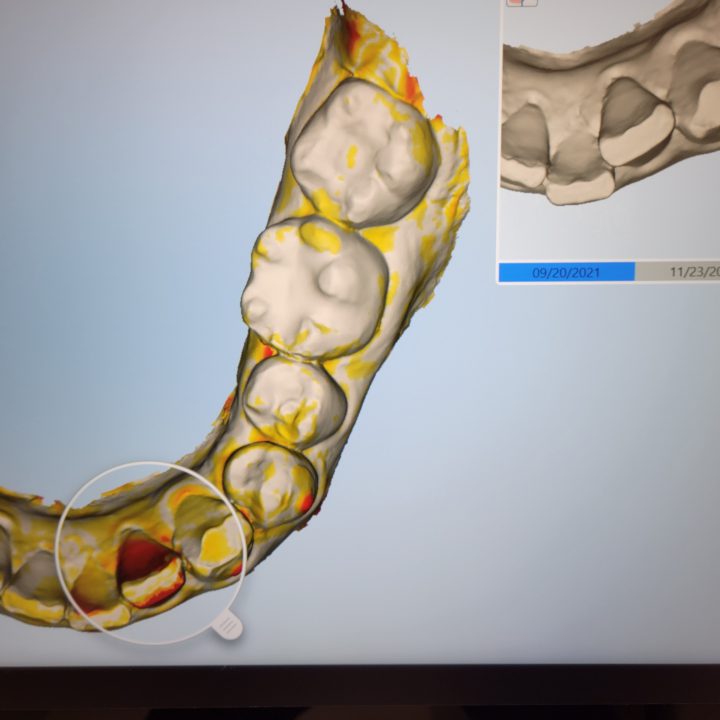

↑これはiTeroのNIRIモードを使用したスキャナーデータです。

右上のレントゲンのような白黒の画像(NIRIモード)では、

歯と歯の間、真っ白に写った部分、

虫歯、もしくは虫歯になりかけているところを診ることが出来ます。

虫歯を可視化できる一つのツールです。

中には、すぐに削る必要がない経過観察をしてもよい歯もあります。

が、肉眼では分かりにくい場合など、初期の診断に有効です。